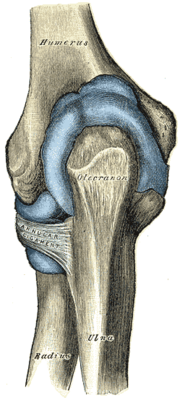

![]() Left elbow-joint, showing anterior and ulnar collateral ligaments. | |

المرفق إنگليزية: Elbow هي عظمة مفصلية تربط عظمة العضد مع عظمتي الزند و الكعبرة. وتكون أماكن الالتقاء الثلاثة، ثلاثة مفاصل أصغر وتسمح هذه المفاصل الصغيرة بحركات معينة، حيث يسمح مفصلا العضد ـ الزند والعضد ـ الكعبرة للشخص بثني الساعد إلى أعلى وأسفل، بينما يسمح مفصلا الكعبرة ـ الزند والعضد ـ الكعبرة بدوران الساعد وكذلك راحة اليد أعلى وأسفل.

يحيط بمفصل الكوع كبسولة من نسيج متين. وتقوم هذه الكبسولة مع عدد من الأنسجة القوية الحبلية الشكل التي تُعرف بالأربطة بالمحافظة على العظام في أماكنها. ويعمل السائل الزيلي بمثابة مزلق لتقليل الاحتكاك عند الكوع.